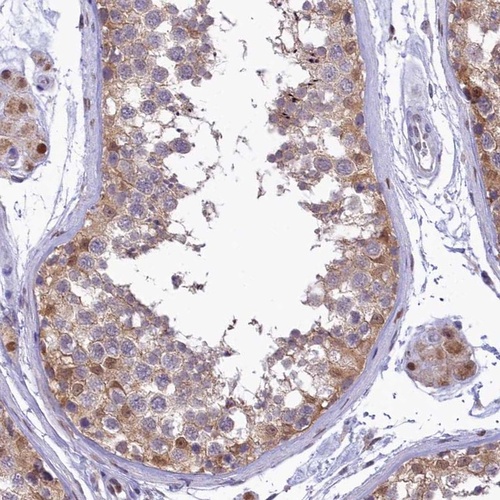

Immunohistochemical staining of human testis shows moderate cytoplasmic and nuclear positivity in seminiferous ducts and Leydig cells.